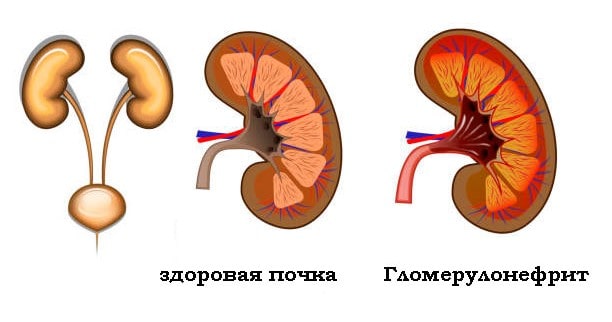

Механизм остро го диффузного гломерулонефрита